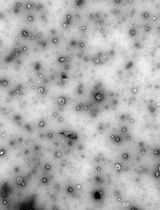

Graphical overview of extracellular vesicle (EV) isolation from plasma samples. (A) Flowchart of the isolation of extracellular vesicles from plasma, detailing plasma preparation and EV purification. (B) Transmission electron microscopy (TEM) image of EVs isolated from human plasma samples. Scale bar, 100 nm.